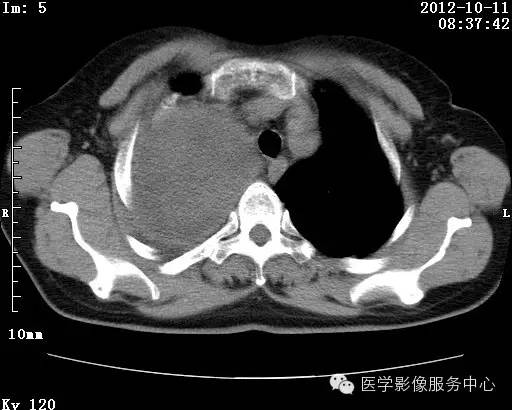

【病例】右肺巨大错构瘤1例CT影像表现

病史:女 65岁咳嗽咳痰 右肺巨大肿块就诊。

错构瘤的主要组织成分包括软骨、脂肪、平滑肌、腺体、上皮细胞,有时还有骨组织或钙化。错构瘤一般为实质致密的球形、卵圆形,也可以是分叶状或结节状,大多数直径在3cm以下。

瘤内出现“爆米花样钙化”是诊断的主要指标之一。早期的点状、斑片状及结节状钙化 随时间增加钙化数量及范围会增加,最终可能演变 为爆米花样钙化;

另一项主要指标是瘤测得脂肪成分是诊断错构瘤。